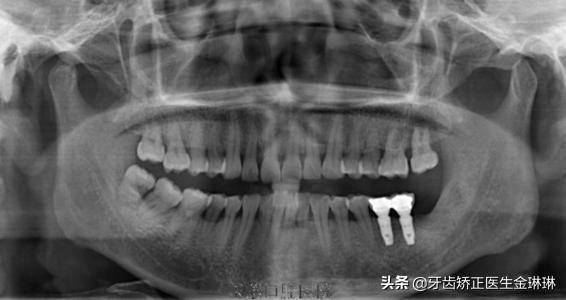

臨床上開展種植技術(shù)需要配備較高的設(shè)備環(huán)境,例如大型X線診斷設(shè)備、臨床手術(shù)設(shè)備、技工設(shè)備、手術(shù)支持設(shè)備以及制作時(shí)需要的一些獨(dú)特的較貴重的種植牙修復(fù)材料。

種植牙手術(shù)前醫(yī)生要為缺牙者拍攝X光片、CT片,檢查牙齒的缺失情況確定調(diào)節(jié)方案,同時(shí),還需測(cè)量缺牙者的血壓、血糖等體征指標(biāo)來掌握患者身體情況;手術(shù)后密切觀察缺牙者的術(shù)后反應(yīng)及跟進(jìn)控制。